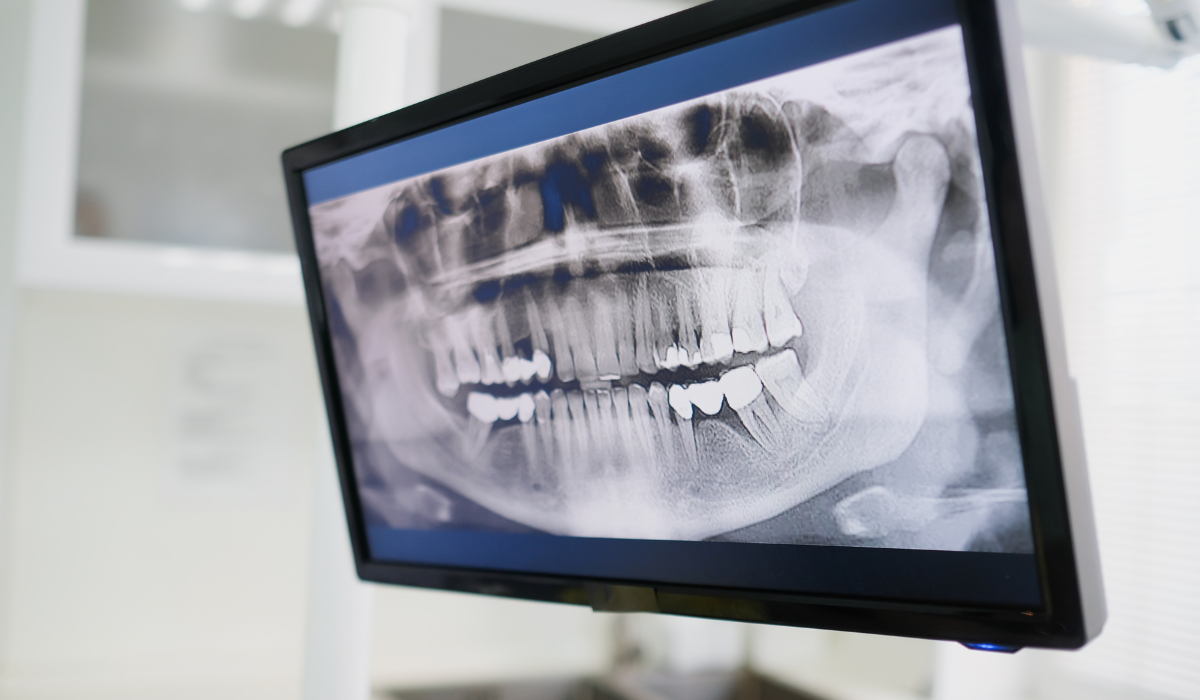

구강 건강 상태 확인

- 잇몸 염증 여부 확인

- 잇몸 뼈 상태 확인

- 구강 위생 상태 확인